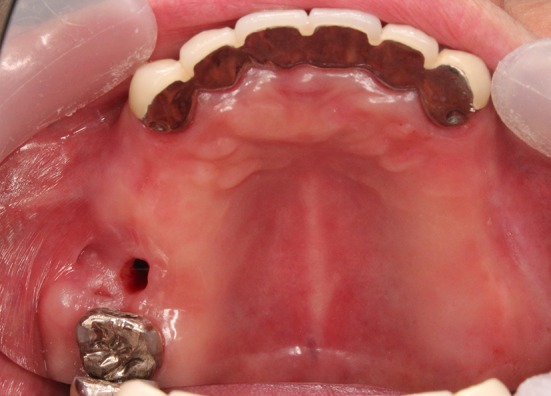

Fig. 1.

Image obtained before the closure of the palatal fistula in case 1. The fistula exists near the palatal median